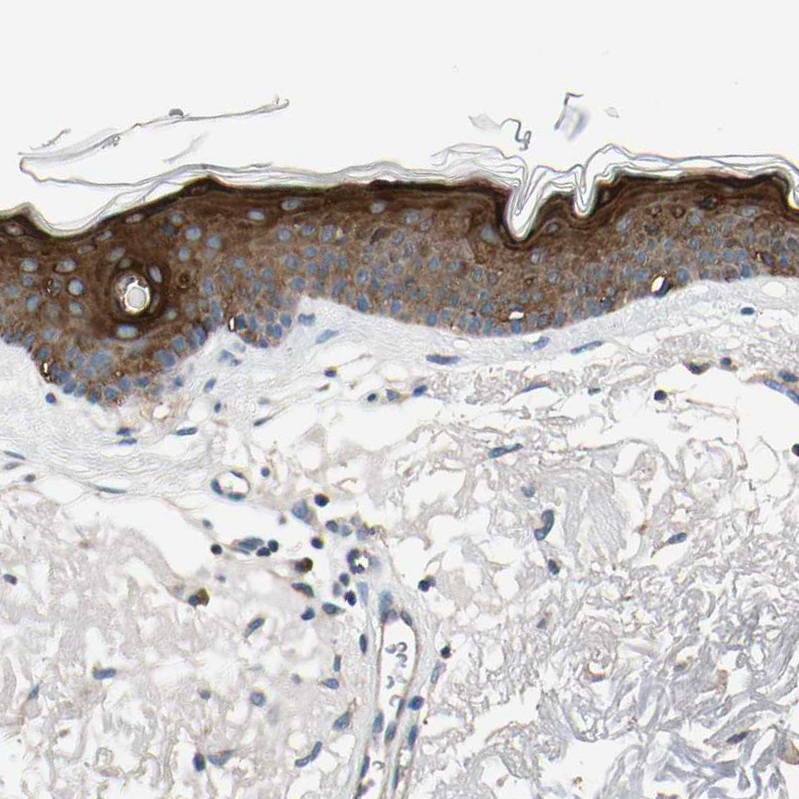

HPA008026

serine/threonine kinase 40

Anti-STK40 Antibody

Polyclonal Antibody against HUMAN STK40